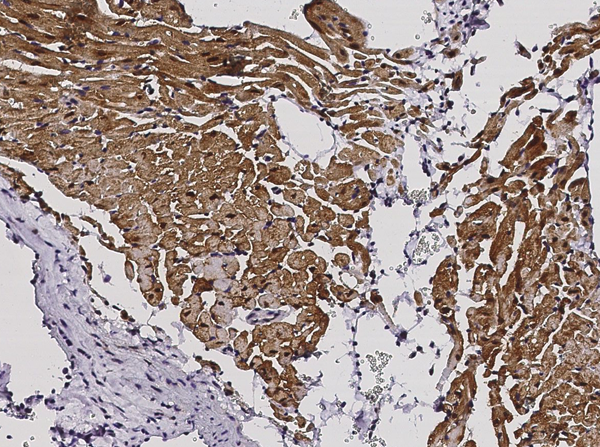

IHC (Immunohistochemistry)

(Immunochemical staining of mouse S100A1 in mouse heart with rabbit monoclonal antibody (1:200, formalin-fixed paraffin embedded sections).)